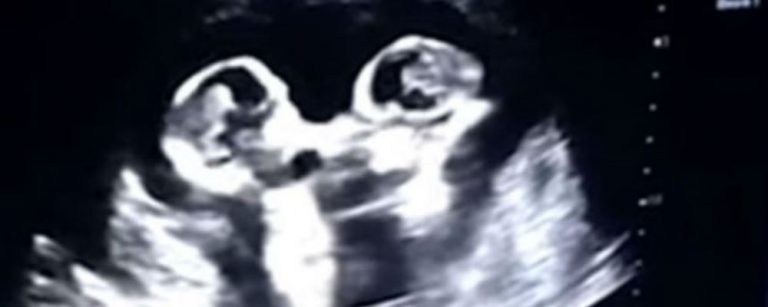

Los bebés suelen dar patadas mientras se encuentran en el útero de la madre, lo que no es ninguna novedad. Pero ahora una ecografía ha captado la tierna «pelea» entre dos gemelas a las que todavía le faltan varias semanas para nacer.

Una embarazada de cuatro meses se realizó una ecografía, en un centro de salud ubicado en la ciudad china de Yinchuan. Todo transcurría con normalidad hasta que su marido, que filmaba el monitor con el que se realizaba el control rutinario, descubrió que -a juzgar por sus movimientos- sus gemelas «parecían estar peleándose».

Tao, el padre de las bebés, explicó al periódico chino The Paper que le parecía muy divertido ver «una pelea de ellas como si estuvieran en un ring de boxeo».

El padre de la gemelas, relató que durante otra ecografía ambas parecían estar dándose un fuerte abrazo. Sin duda, serán unas niñas muy especiales, consigna 20 Minutos.

La particular escena se produjo a fines de 2018, y ahora que las niñas nacieron, el 8 de abril, ha sido ampliamente compartida en las redes sociales chinas.